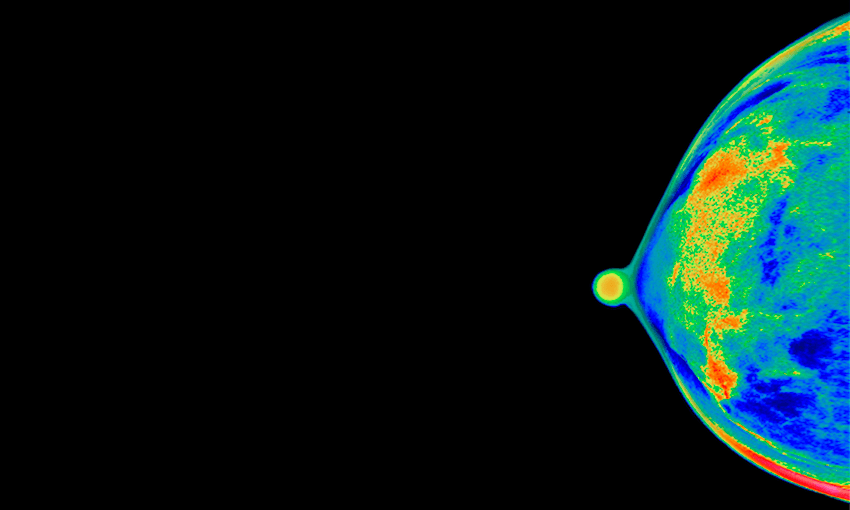

Dr Saini: A mammogram is an x-ray. It takes two images of each breast and it requires a squeezing of the breasts between two plates so that the breast tissue can be spread out and a radiologist can identify changes including breast cancer. Mammograms look through the breast tissue.